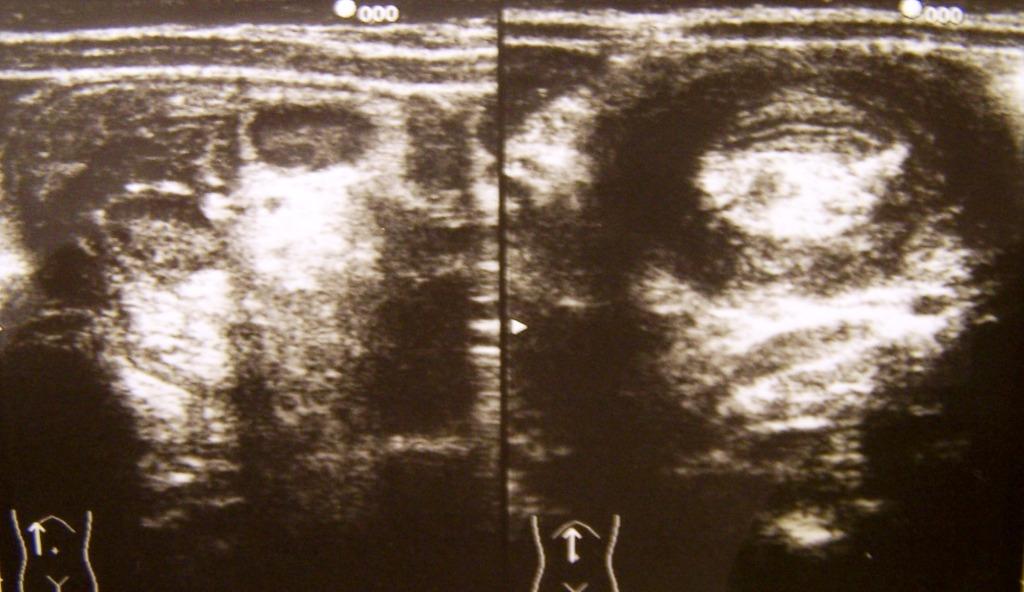

Il quadro ecografico dopo il clisma si modifica un poco (riduzione dell�asse maggiore della massa e comparsa di minima quantit� di liquido nel suo contesto) (Figura 2a). Il segnale doppler � ben apprezzabile (Figura 2b).

Figura 2 (a). Quadro ecografico dopo clisma a bassa pressione di sol. fisiologica calda.

Figura 2 (b)Segnale doppler dopo clistere.